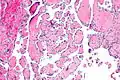

Pathology

Histopathology Images